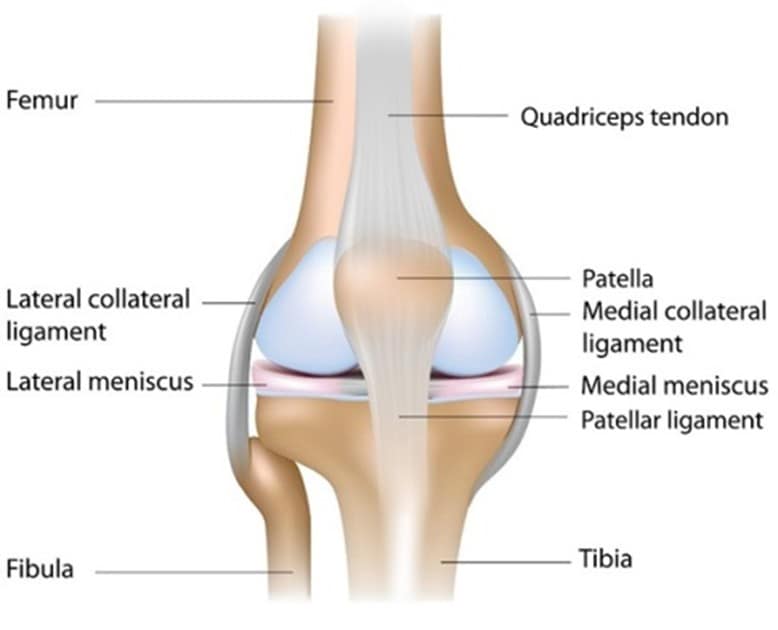

The knee is one of the largest joints in the body that functions as a complex hinge between the upper and lower parts of your leg. Your knee is comprised of four bones: the femur (thigh bone), tibia (shin bone), patella (knee cap) and the fibula (a smaller bone in your lower leg). The surfaces of the four bones in contact with one another are covered by articular cartilage. The cartilage is designed to allow the bone surfaces to move over each other smoothly. The knee should normally have a painless range of movement.